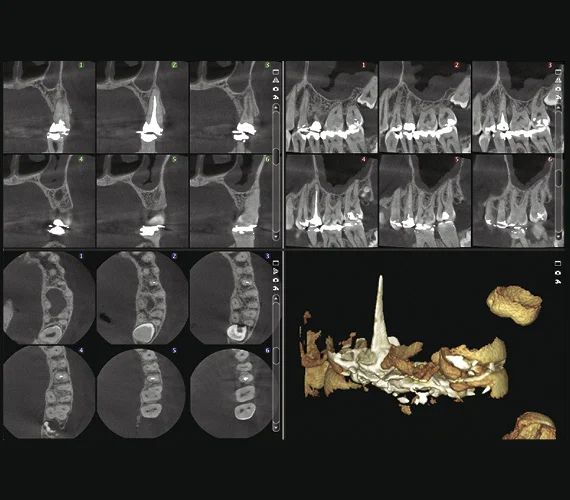

Специальный эндодонтический режим визуализации

Качество изображения имеет большое значение, но состоит из мелочей. Эндодонтический режим визуализации идеально подходит для съемки мелких анатомических деталей. Он предлагает исключительно высокое разрешение с размером вокселя 75 мкм.